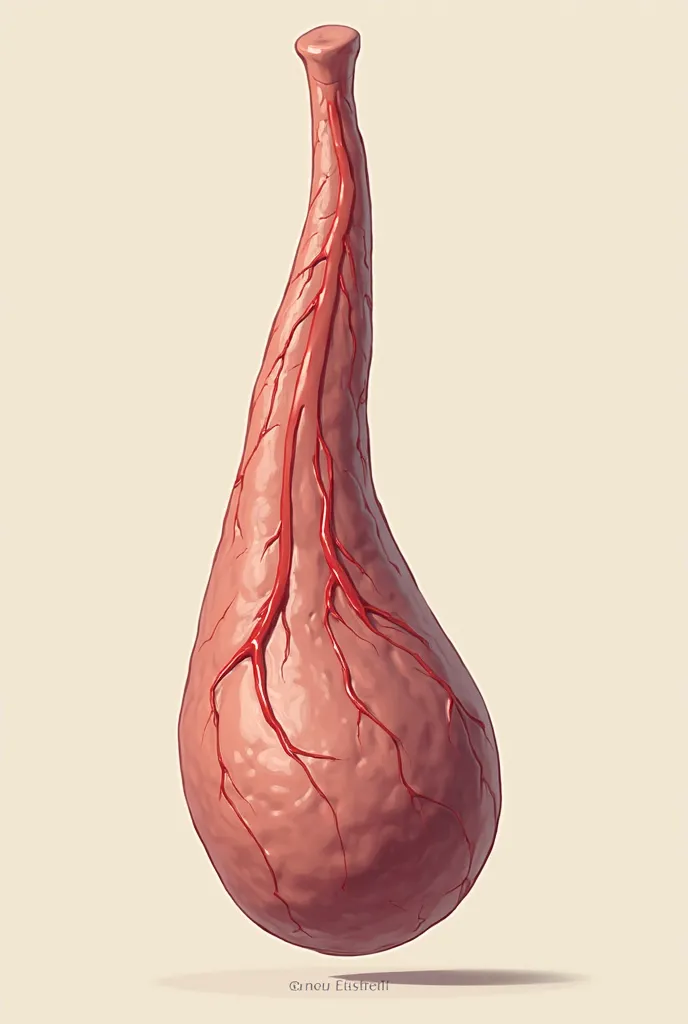

A diagram of the anatomy of the human body

Realice un dibujo de la piel. Coloque las siguientes referencias: Epidermis Fermis Hypodermis Keratinized squamous stratified epithelium Hair Sebaceous gland Sweat gland Pilo erector muscle Connective tissue Blood vessels Nerves Adipocytes

Epidermis Fermis Hypodermis Keratinized squamous stratified epithelium Hair Sebaceous gland Sweat gland Pilo erector muscle Connective tissue Blood vessels Nerves Adipocytes